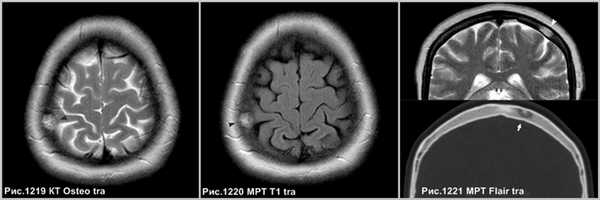

Гемангиома в плоских костях черепа - не частое образование, которое располагается преимущественно в диплоическом слое. Имеется разряженное строение губчатого вещества и толстые костные трабекулы, радиально расходящиеся в стороны. Очаг разряжения губчатого вещества в толще диплоического слоя определяется как зона↓плотности на КТ (стрелка на рис.1221) и↑МР-сигнала на Т2 и Flair (головки стрелок на рис.1219-1221).

Крупная гемангиома в теле L5 позвонка, распространяющаяся на всё его тело, приводящая к перестройке губчатого вещества кости, с разряжением губчатого вещества и наличием вертикальных утолщенных костных балок (головки стрелок на рис.1222,1223). Гемангиома в теле позвонка, имеющая жировую интенсивность МР-сигнала - ↑сигнал по Т1, с обозначением контура на последовательности в противофазе (головка стрелки на рис.1224), и имеющая выпадение МР-сигнала в режиме Т2 с жироподавлением (стрелка на рис.1224), что соответствует жировой ткани в гемангиоме.